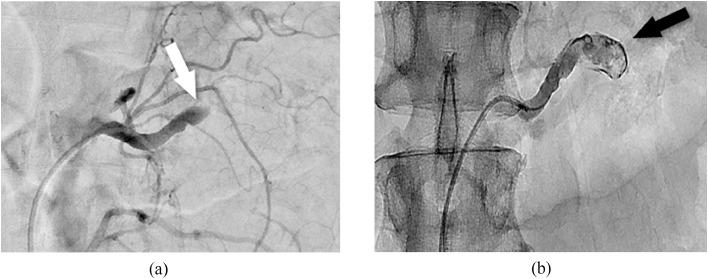

Spontaneous renal artery thrombosis is a rare cause of flank pain and can have fatal consequences. We report a case of acute renal artery thrombosis in a 61-year-old man who experienced flank pain and had no medical history. A contrast-enhanced computed tomography scan revealed total thrombotic occlusion of the left renal artery. The patient was taken to interventional radiology, and an urgent catheter-directed thrombolysis of the renal artery was performed. The procedure was successful, with the subsequent arteriogram demonstrating a substantial decrease of the thrombus extent and the recanalization of the left renal artery. This case highlights that emergency renal artery thrombolysis is an effective and safe treatment for acute occlusion of the renal artery.

自发性肾动脉血栓形成是引起胁腹疼痛的罕见原因,且可能导致致命后果。我们报告一例61岁男性急性肾动脉血栓形成病例,该患者出现胁腹疼痛且无病史。增强计算机断层扫描显示左肾动脉完全血栓闭塞。患者被送往介入放射科,紧急进行了肾动脉导管直接溶栓术。手术成功,随后的血管造影显示血栓范围大幅减小,左肾动脉再通。该病例表明,急诊肾动脉溶栓术是治疗肾动脉急性闭塞的一种有效且安全的方法。